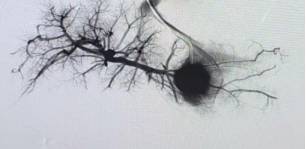

經頸靜脈造影

術前,放射科與超聲醫學科借助超聲探查及CT血管三維重建技術,明確病變所在部位;隨后,消化內科開展經肝靜脈造影,對病變血管進行精準定位,為手術繪制“血管地圖”;麻醉科與重癥醫學科團隊為手術全程提供保障。

消化內科介入團隊通過靜脈穿刺后實行肝臟靜脈造影,明確血管病變范圍,評估被搭橋段血管是否滿足吻合條件。小兒外科團隊術中探查,再次明確腹腔內病變程度,在血管條件滿足搭橋吻合的前提下,由血管外科團隊協助獲取患兒右側頸內靜脈作為搭橋血管。頸內靜脈是頸部引流顱內組織血流的重要靜脈,具有更粗更直且血管內無瓣膜等特點。雙側頸內靜脈可相互代償,在正常人體獲取一側頸內靜脈可由對側血管代償引流。因此,頸內靜脈是Meso-Rex手術較為理想的搭橋血管。但頸部存在著人體重要且復雜的血管、神經、肌肉、氣管、腺體以及淋巴系統等,頸內靜脈又在較深的頸部肌肉深面,要想在完全不損傷頸部組織前提下獲取深部頸內靜脈,對術中精細操作要求極高。